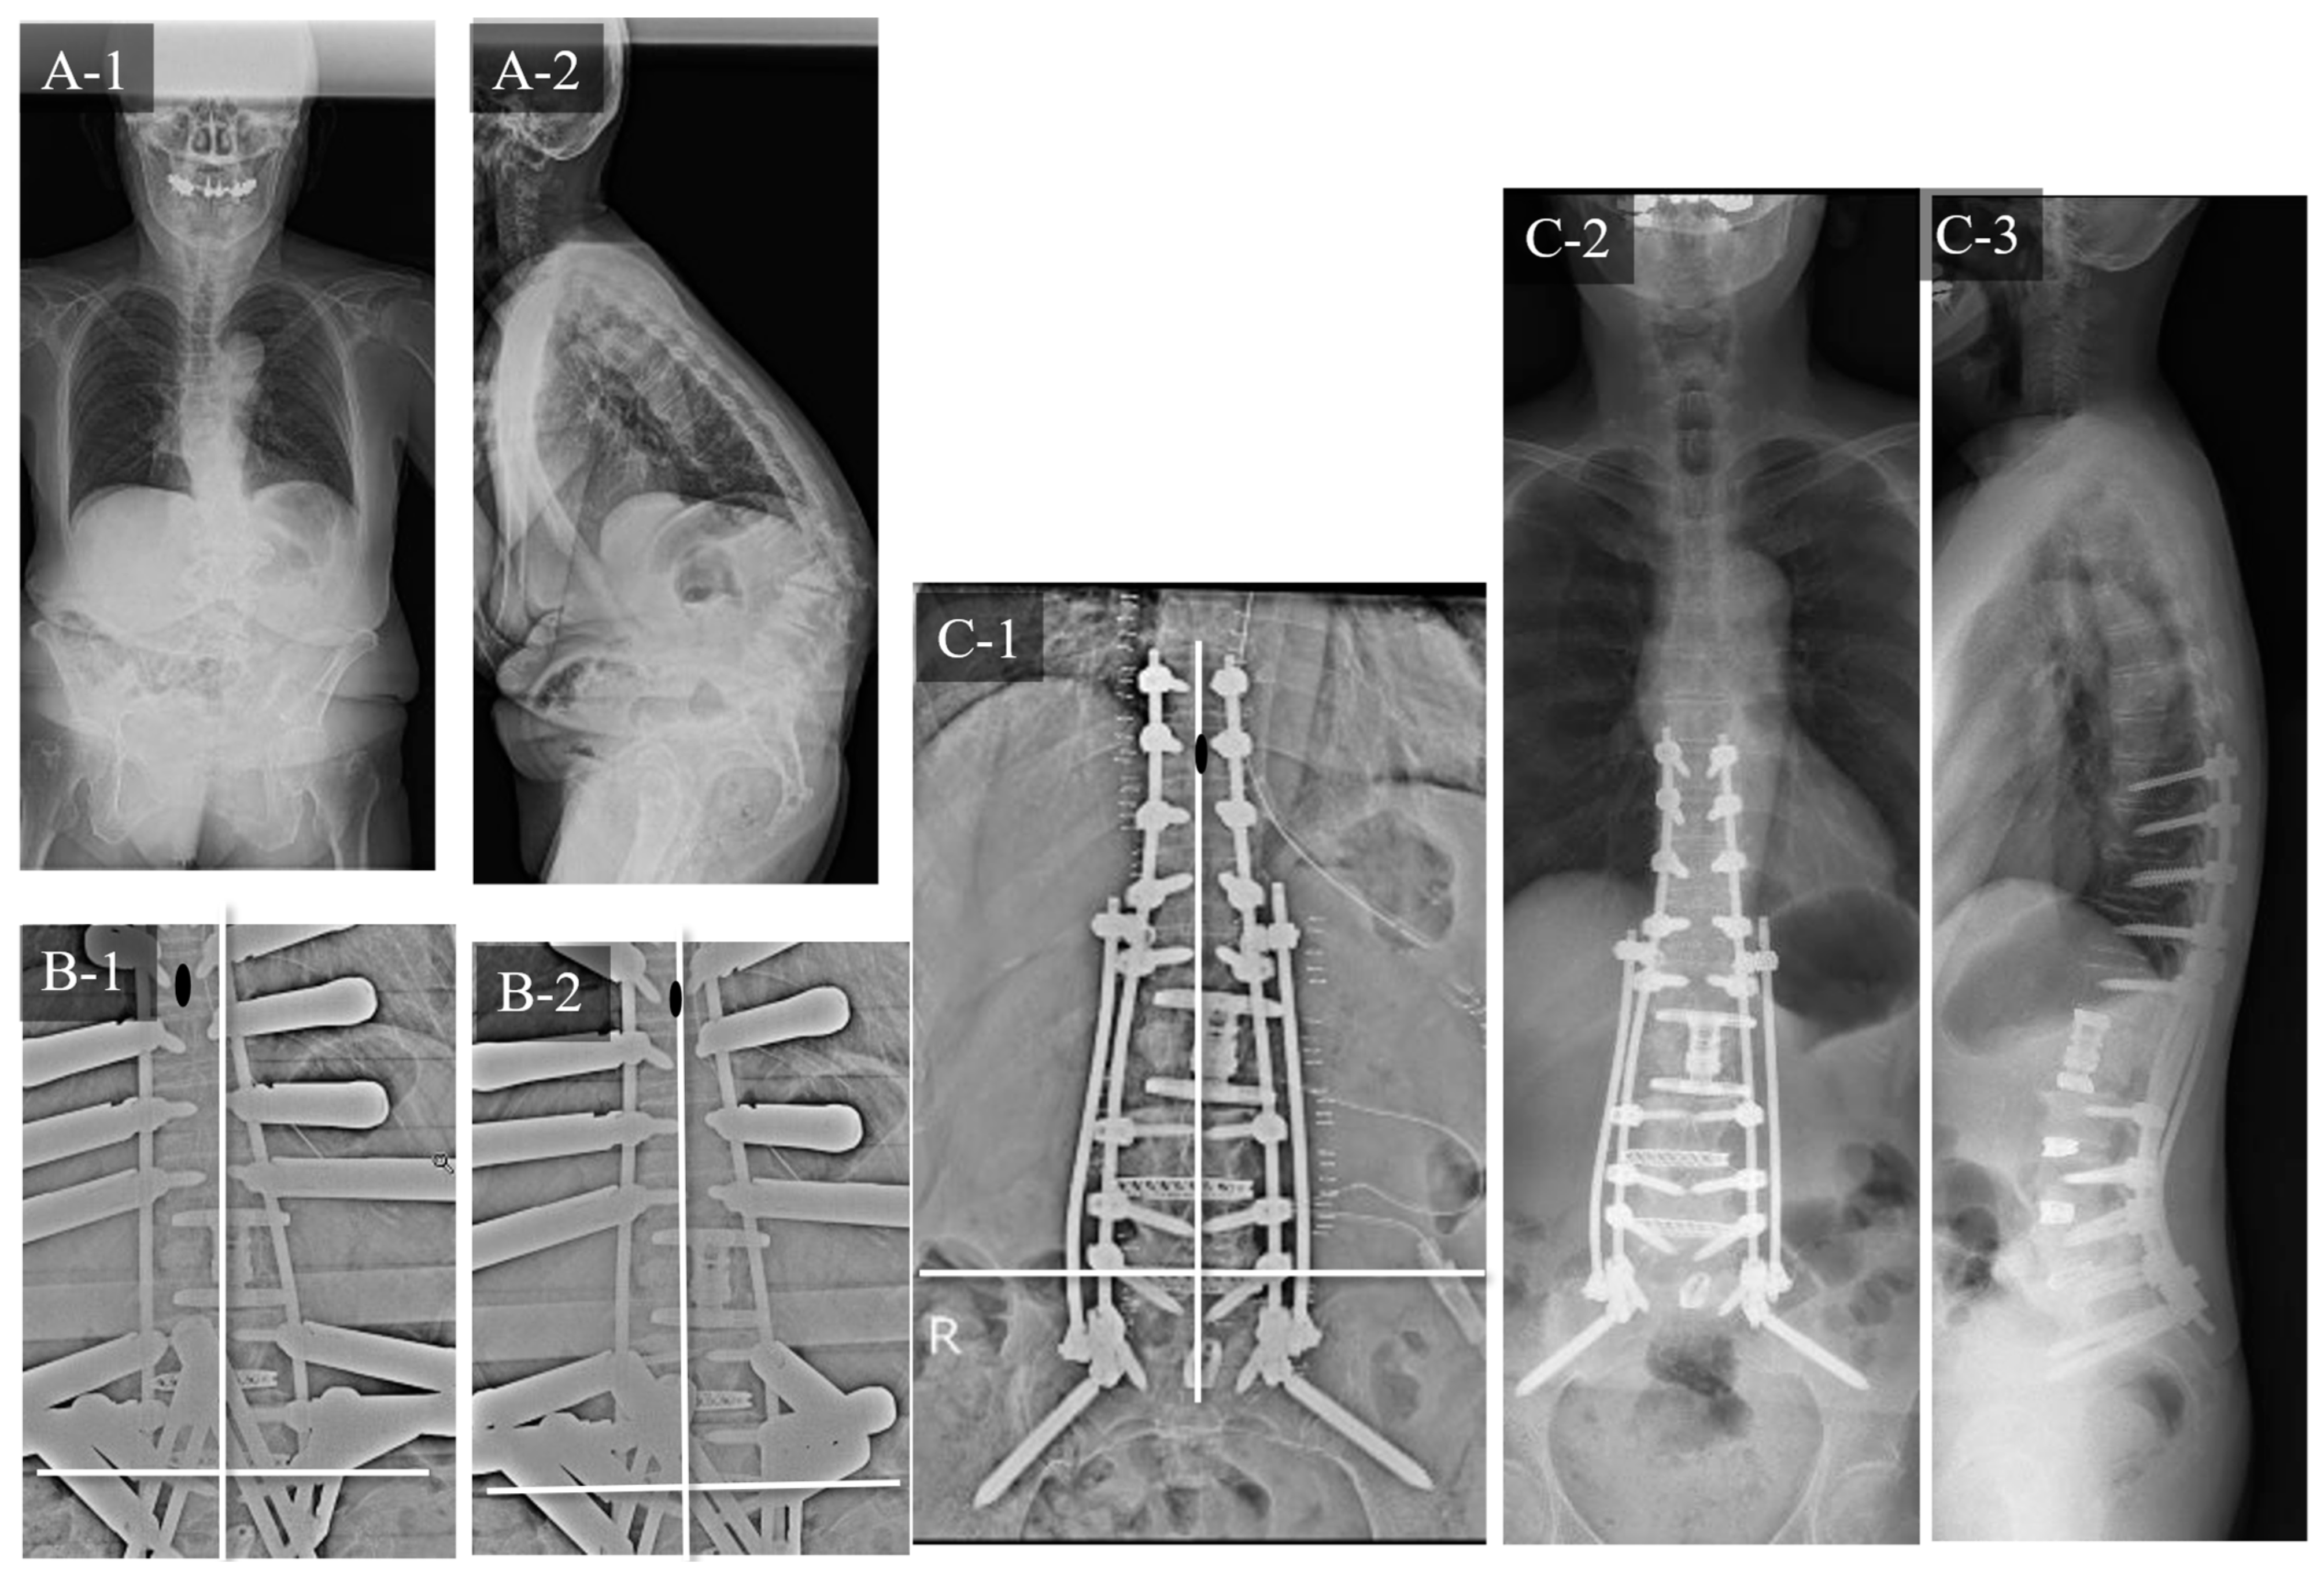

3.1. Case Study 1: RR